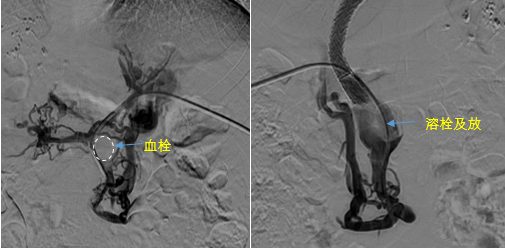

在西安國(guó)際醫(yī)學(xué)中心醫(yī)院,韓國(guó)宏教授對(duì)李女士進(jìn)行了細(xì)致的問(wèn)診及檢查,在CT圖像上仔細(xì)的分析,針對(duì)患者特殊的病情制定了詳細(xì)的治療方案。第一次進(jìn)入手術(shù)室,在DSA的監(jiān)測(cè)下,造影過(guò)程中門靜脈血栓的輪廓逐漸顯現(xiàn)出來(lái),見多識(shí)廣的醫(yī)生們也大吃一驚,發(fā)現(xiàn)遠(yuǎn)端脾靜脈及腸系膜上靜脈也存在大量血栓?;颊叩氖彻芪傅嘴o脈曲張非常嚴(yán)重,疏通堵塞的門靜脈已是刻不容緩。

見此情形,韓國(guó)宏教授憑借豐富的臨床經(jīng)驗(yàn)很快調(diào)整了策略,在超聲診療中心的協(xié)助下進(jìn)行門靜脈右支穿刺,并進(jìn)行造影,看到目標(biāo)血管后,韓國(guó)宏教授用“明修棧道,暗渡陳倉(cāng)”的方法,讓來(lái)自脾臟和胃腸的血流終于暢通的回流到了肝靜脈。通過(guò)血流的沖刷以及抗凝溶栓藥物的作用,幾日后復(fù)查造影發(fā)現(xiàn)門靜脈血栓已逐漸變小,不會(huì)對(duì)回流到肝臟的血流產(chǎn)生大的阻礙作用,門靜脈的壓力顯著減小,患者再次出血的幾率也隨之降低。幾經(jīng)周折,這顆“定時(shí)炸彈”終于被拆除,李女士和她的家人多年來(lái)心里的石頭也終于落地。